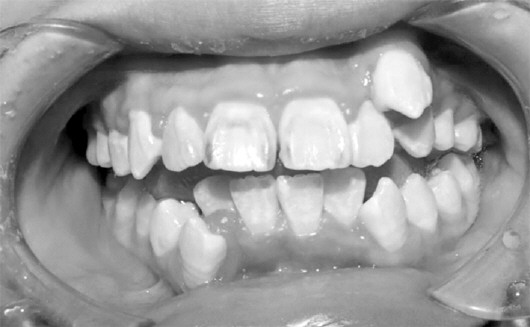

二、临床表现

本病好发于前牙唇侧的龈乳头和龈缘。唇侧牙龈肿胀较明显,龈乳头常呈球状突起,颜色暗红或鲜红,光亮,质地软,探诊出血明显。龈沟可加深形成龈袋,但附着水平无变化,亦无牙槽骨吸收。患者的主诉症状常为刷牙或咬硬物时出血、口臭等。

初诊